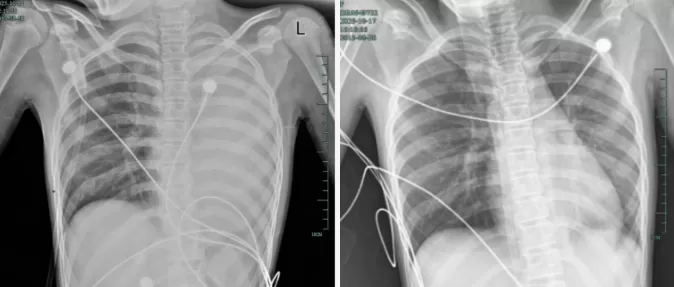

治疗前后影响对比,左肺从“白肺”到正常状态。

呼吸急促、胸闷胸痛,体温38.5℃,只能靠5L/min的面罩吸氧维持血氧,胸片显示左肺已完全呈 “白肺” 改变,肺部炎症进展迅猛。